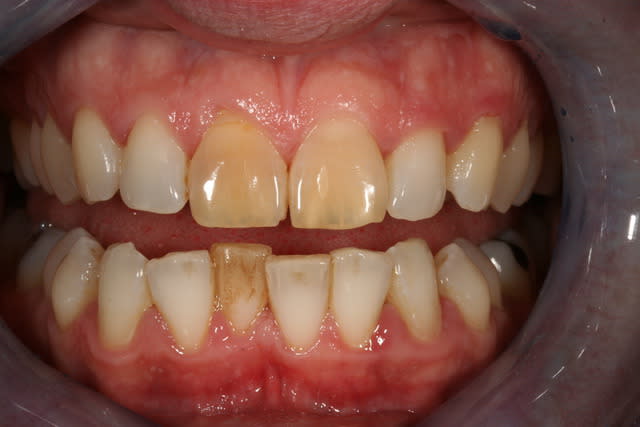

Cas simple et pourtant ... j'ai été obligé de prendre un risque . Lequel ?

Indice : on lui avait proposé la dévit et une céram .

C'est un blanchiment interne comme si l'endo était faite (après recherche effrénée d'un hypothétique canal), et après contrôle +++ d'une isolation +++ . La patiente n'a aucun souvenir d'un traumatisme sur cette dent .

Si on décide d'être le moins invasif , j'ai jugé raisonnable de tenter quand même malgré l'impossibilité de repérage de l'entrée du canal . Faire une facette c'est passer un cap , et je n'ai de prothésiste capable de reproduire les stries visibles sur la photo de départ de tout façon donc je n'ai compté que sur moi même .